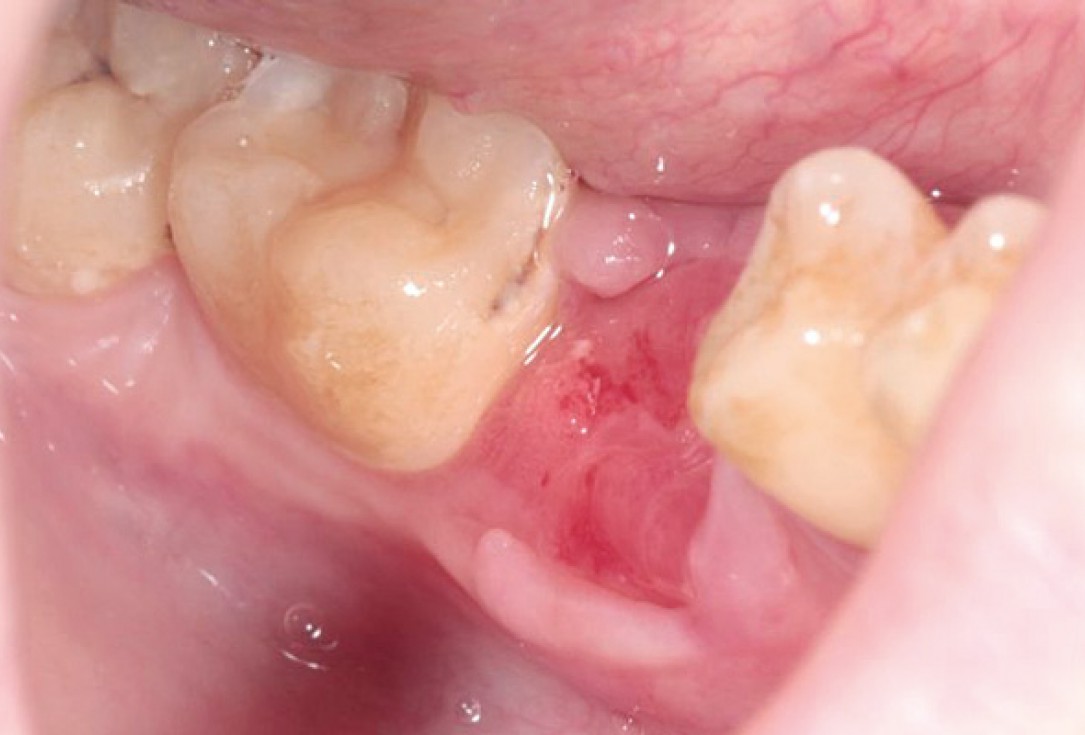

Delayed implant placement with GBR and soft tissue augmentation at the aesthetic area  -  2 years follow up – Dr. H. Maghaireh & Dr. V. Ivancheva

Initial situation - broken and missing upper right central incisor (UR1). This tooth was removed long time ago and there were signs of bone loss and resorption due to the bone remodelling. Patient was also undergoing orthodontic treatment due to the loss of mesio-distal space.